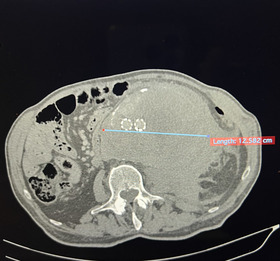

Ανεύρυσμα θεωρείται οποιαδήποτε διάταση αγγείου μεγαλύτερη του 50% της φυσιολογικής του διαμέτρου. Στην περίπτωση της κοιλιακής αορτής και συγκεκριμένα στο υπονεφρικό τμήμα της, δηλαδή κάτω από το επίπεδο των νεφρικών αρτηριών η αορτή έχει φυσιολογική διάμετρο περίπου 2cm, λίγο μεγαλύτερη στους άνδρες, λίγο μικρότερη στο γυναικείο φύλλο. Θεωρείται λοιπόν ανεύρυσμα όταν η αορτή ενός ενήλικα έχει διάμετρο 3cm και πάνω.

α. διάμετρος >5cm σε γυναίκα και >5,5cm σε άνδρα,

ΡΗΞΗ ΑΝΕΥΡΥΣΜΑΤΟΣ

Επιπλοκή ενδαγγειακής αποκατάστασης ανευρύσματος που χειρουργήθηκε αλλαχού,

– ρήξη – ανοικτή αποκατάσταση